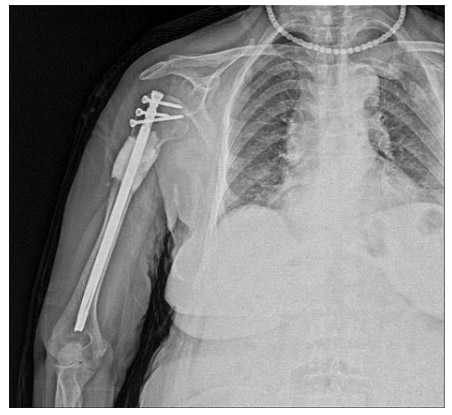

CASE 4: Risk of fracture in the right arm (humerus) due to metastasis of kidney cancer (RCC - Renal cell carcinoma).

Post-surgery: The X-ray shows the procedure of removing the tumorous portion of the bone in one piece with clean margins, filling the resulting cavity with bone cement, and reinforcing it with a closed titanium nail.